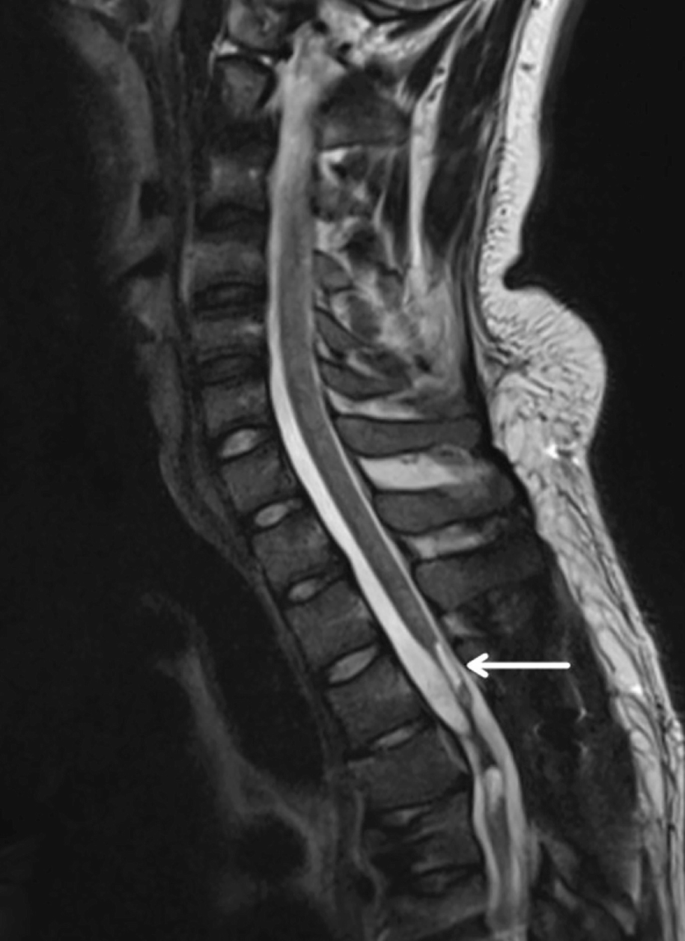

慢性期開(kāi)始于損傷后約3-6個(gè)月,并持續(xù)患者的余生,典型特征是囊腫形成和嚴(yán)重的神經(jīng)膠質(zhì)瘢痕(圖2)。

圖2:X射線圖像顯示慢性期脊髓損傷,通常以囊腫形成為特征,如白色箭頭所示